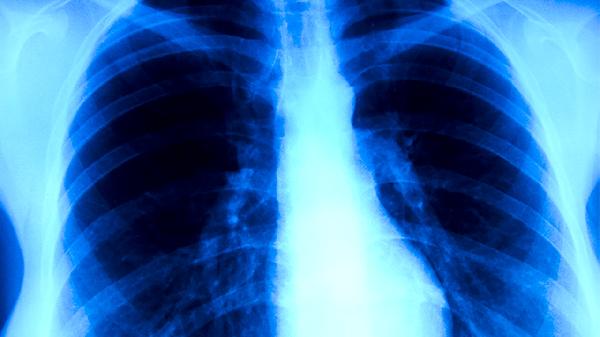

耐药性肺结核是指结核分枝杆菌对一种或多种抗结核药物产生耐药性的肺结核类型,通常由不规范用药、药物吸收不良或基因突变等因素引起。

耐药性肺结核患者应保持均衡饮食,适量增加鸡蛋、瘦肉等优质蛋白摄入,避免辛辣刺激食物。注意室内通风消毒,佩戴口罩防止传播,每日进行适度有氧运动增强体质。治疗期间定期复查胸部CT和痰菌检查,出现咯血、持续发热等症状需立即就医。严格遵循医生制定的个体化治疗方案是治愈的关键。